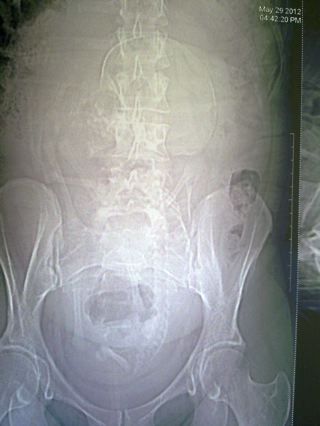

| Dire merci | Photo de la pelvimétrie d'aujourd'hui : pas de doute il est toujours en siège et c'est impressionnant de voir le squelette du bébé en superposition du bien [url=https://www.1cheval.com/membre/services/photos/] ![]() |